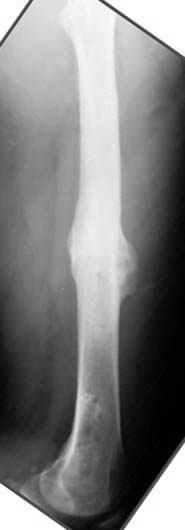

Отправитель: Evgueny Tschekashkin 23 Ноябрь 2004, 21:28

Почему не замена гвоздя с рассверливанием, а аппарат?

хотя даже если бы и инфекция , то nail exchange с рассверливанием канала - вариант дебрайдмента) Я думаю, что последовательность развития событий:

Узкий к-м канал - тонкий гвоздь- усталостный перелом дистальных винтов - развитие нестабильности и как ее результат остеолиз вокруг гвоздя - деформация анатомической оси бедра. Похоже, что я понял почему аппарат, а не новый гвоздь:-)

ЕТ - Изначально костно-мозговой канал бедра был узкий, дальнейшее его рассверливание ещё больше скомпрометирует прочность бедра( латеральный кортекс дистального отломка уже истончен), приведет к дефекту наружной стенки - хотя это только мои догадки - хотелось бы знать мнение Джолдаса о выбранной тактике.